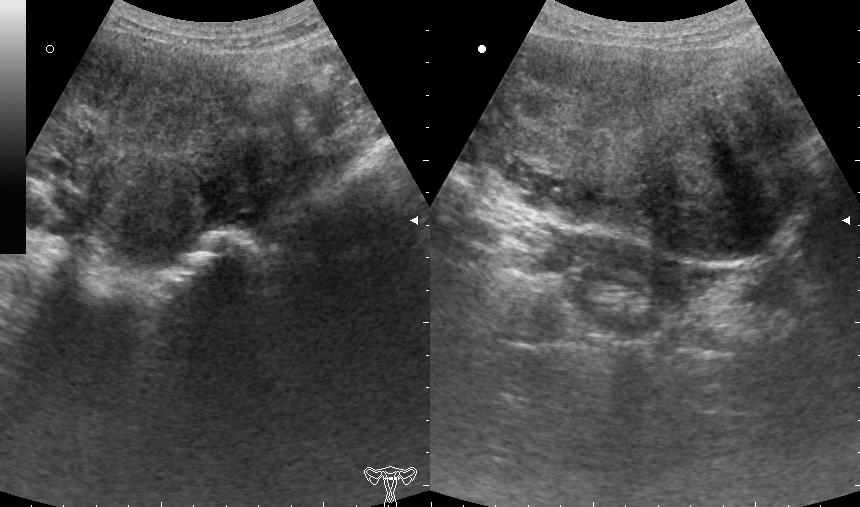

(девушке 23 года. фиброматоз матки)

Почти как на сайте Марио,только возраст другой.Солидное гипоэхогенное негомогенное образование в области придатка слева довольно сложной структуры с усилением(?) кровотока по периферии-я за рак яичника

ещё раз - это матка 23-летней девушки. то есть, ВСЁ это, то что Вы видите, да-да, на весь экран - это матка.

Диагноз - фиброматоз. направлена строго на север и налево. к соседям. (онкодиспансер)